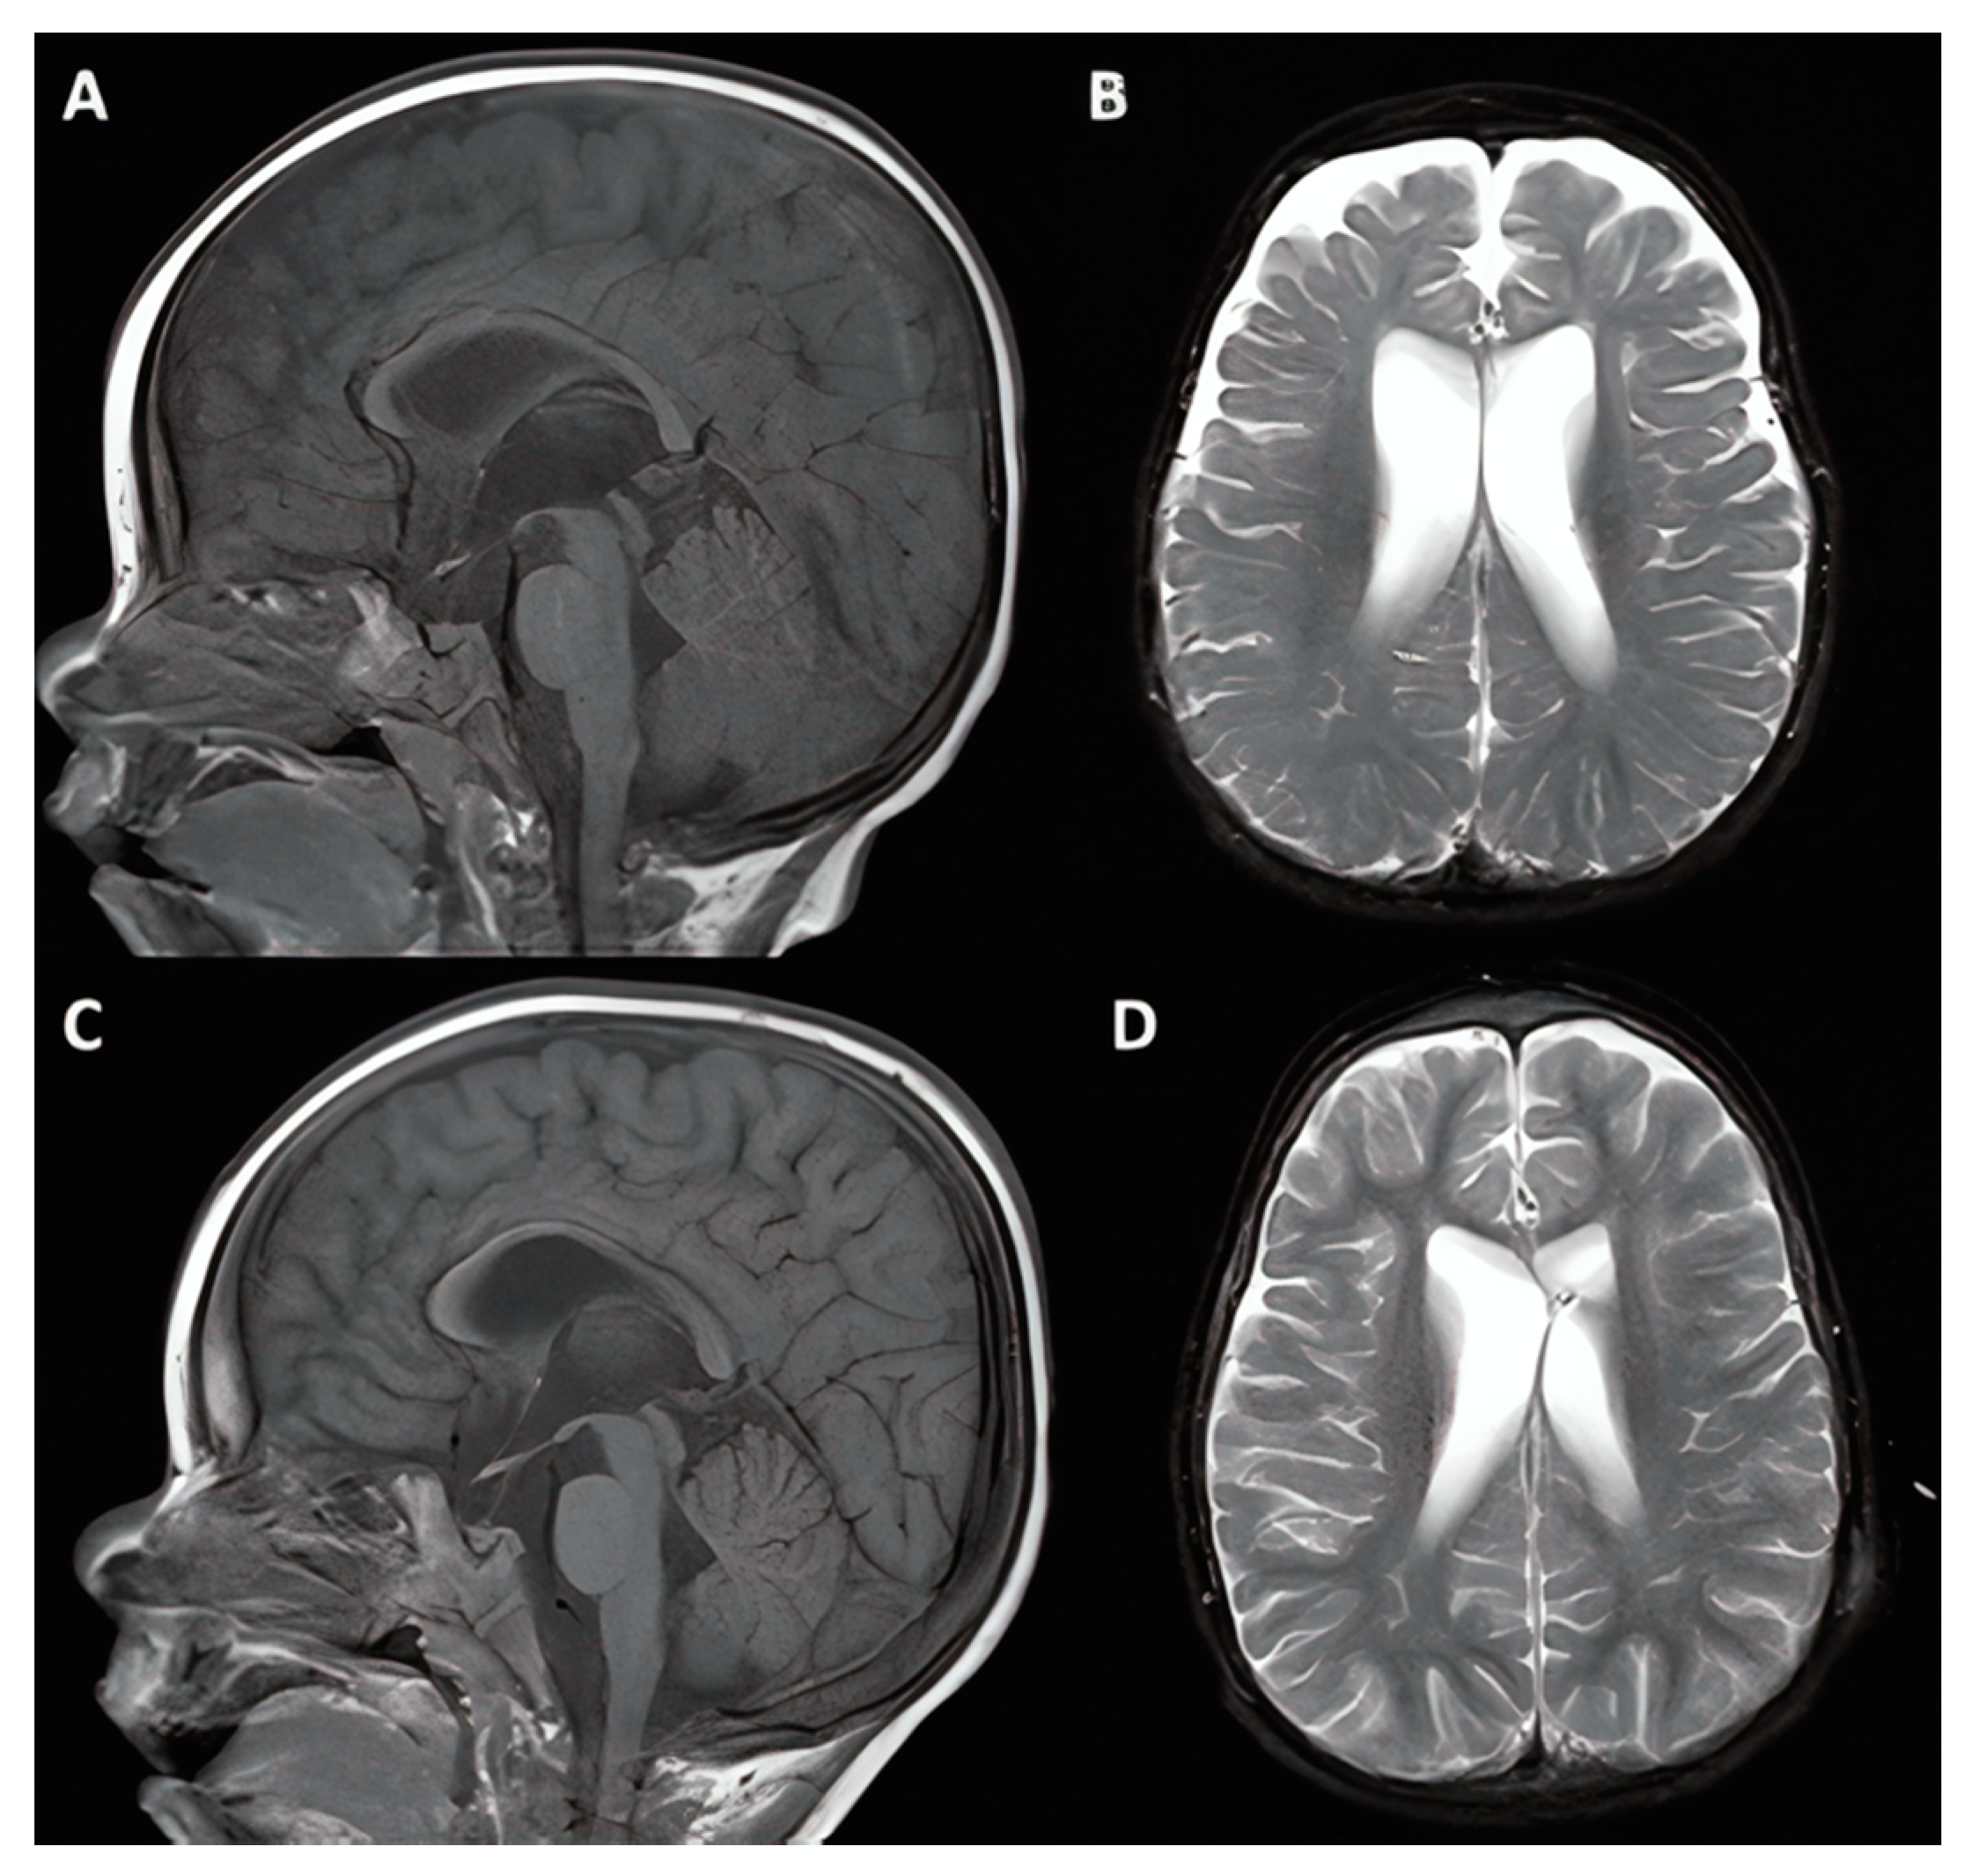

3.1.1. Case #1. Hydrocephalus with Chiari I Malformation

| 1 | 6 y, F |

|